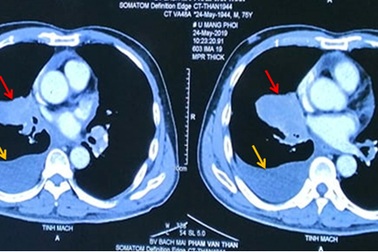

Hút thuốc 25 năm, người đàn ông mắc 2 ung thư cùng lúc di căn nãoÔng Thân đến viện khám vì ho khan, khó thở, khi kiểm tra bác sĩ cho biết ông không chỉ mắc ung thư phổi mà còn mắc thêm ung thư tuyến tiền liệt.